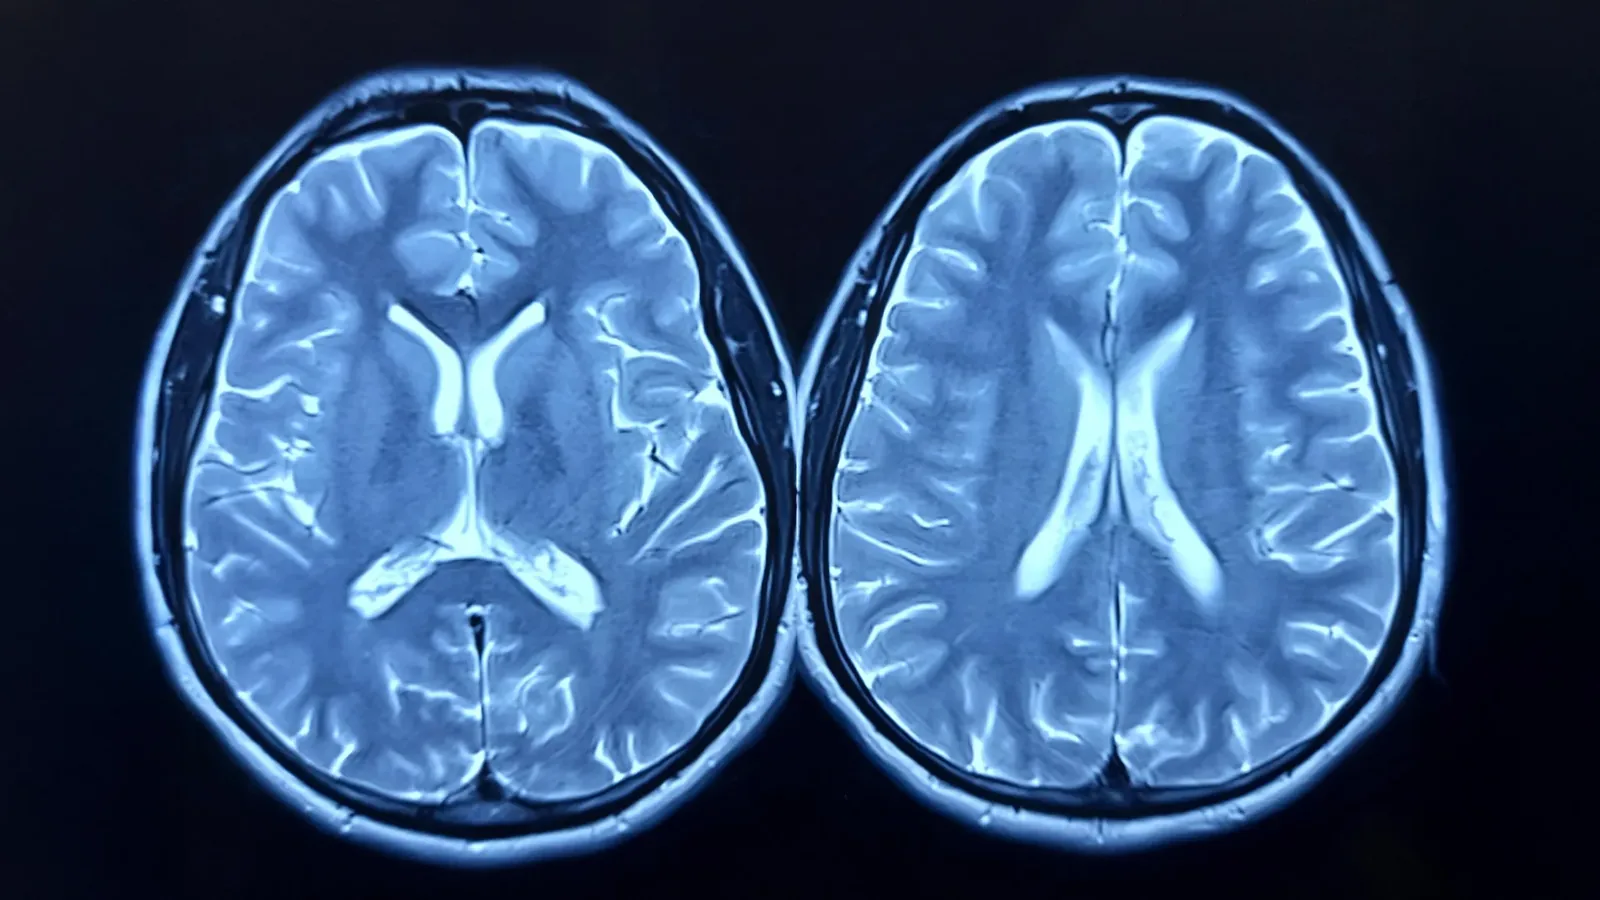

Pandemic Stress Aged Brains Even Without COVID Infection

Recent brain imaging research indicates that the COVID-19 pandemic could have sped up the mental aging process in individuals who never contracted the virus. This comprehensive UK-based investigation demonstrates how the pressures of lockdowns, social isolation, and widespread disruptions might have influenced brain health, particularly affecting older people, males, and those from lower socioeconomic groups. […]